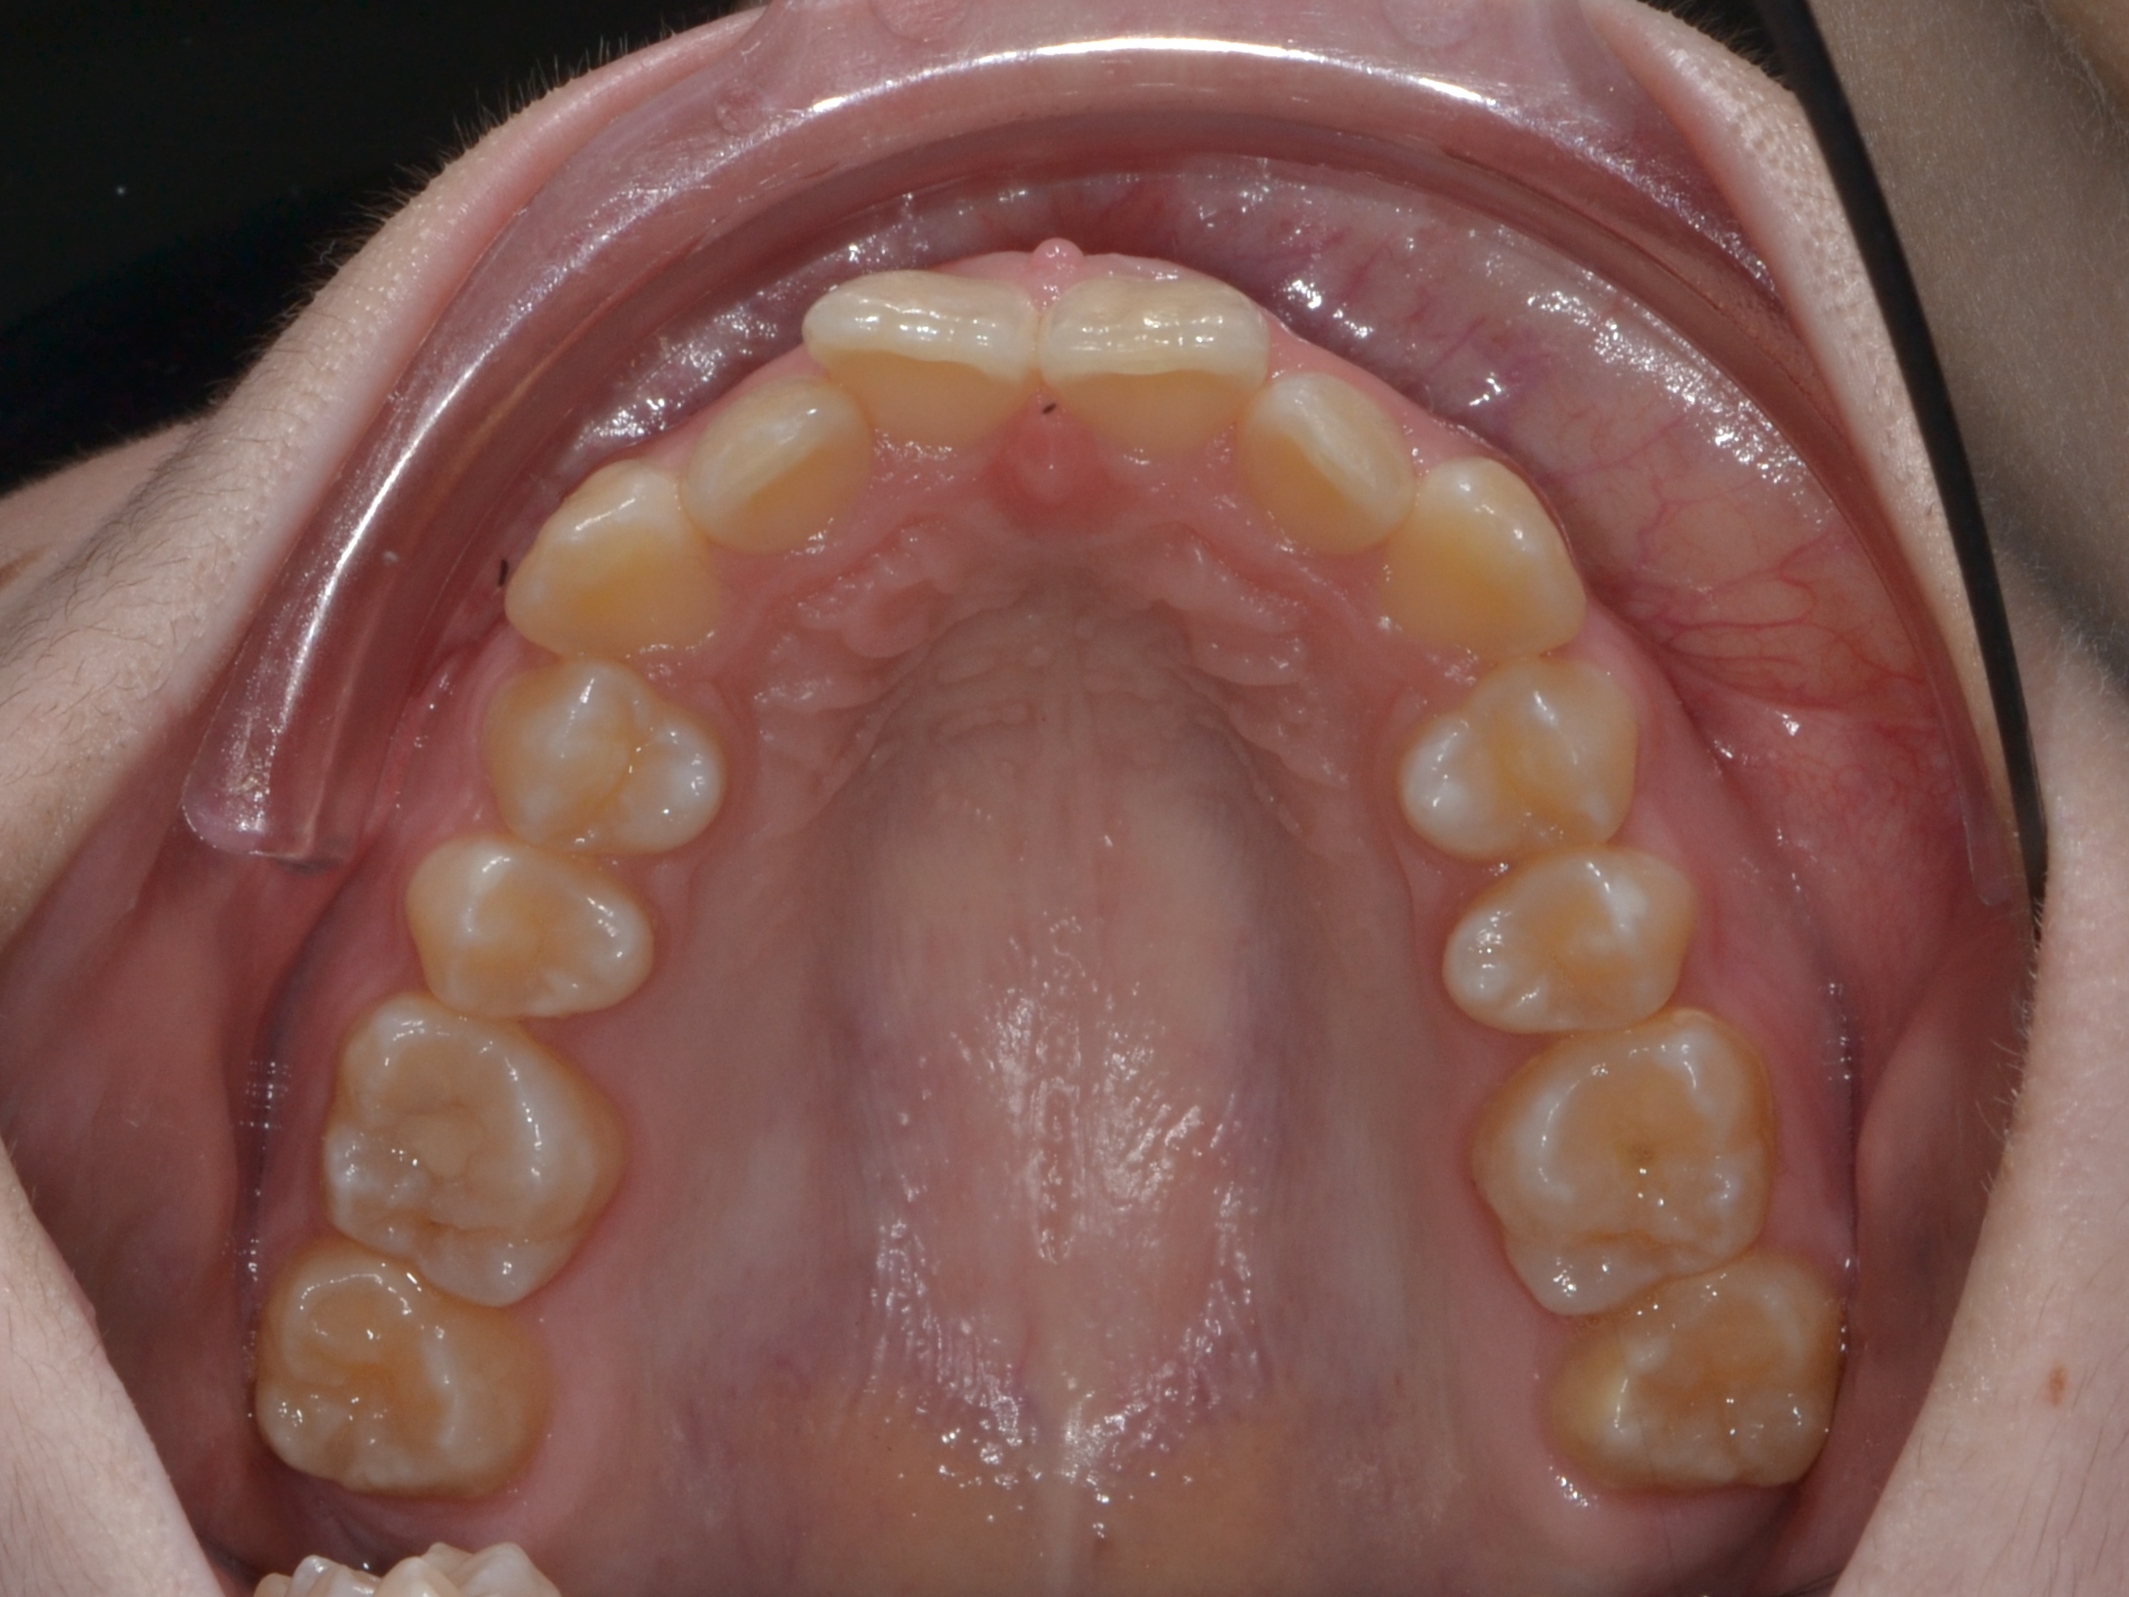

Выявленные проблемы

• Дистальная окклюзия ||(2)

• Глубокое резцовое соотношение

• Скученность фронтальных зубов

• Вестибулярное положение клыков

Брекет-система Ultra